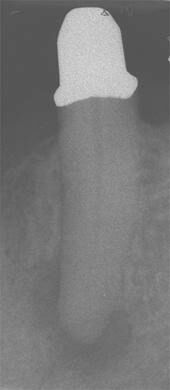

Gleicher Zahn kurz nach erfolgter Wurzelkanalbehandlung. -